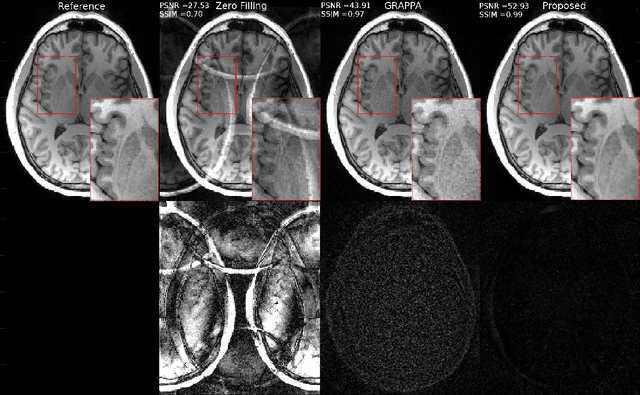

Abstract:Fast data acquisition in Magnetic Resonance Imaging (MRI) is vastly in demand and scan time directly depends on the number of acquired k-space samples. Conventional MRI reconstruction methods for fast MRI acquisition mostly relied on different regularizers which represent analytical models of sparsity. However, recent data-driven methods based on deep learning has resulted in promising improvements in image reconstruction algorithms. In this paper, we propose a deep plug-and-play prior framework for parallel MRI reconstruction problems which utilize a deep neural network (DNN) as an advanced denoiser within an iterative method. This, in turn, enables rapid acquisition of MR images with improved image quality. The proposed method was compared with the reconstructions using the clinical gold standard GRAPPA method. Our results with undersampled data demonstrate that our method can deliver considerably higher quality images at high acceleration factors in comparison to clinical gold standard method for MRI reconstructions. Our proposed reconstruction enables an increase in acceleration factor, and a reduction in acquisition time while maintaining high image quality.